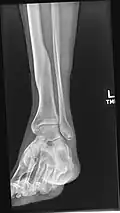

Coronal cross-section through the right ankle showing the lateral malleolus (right) and medial malleolus (left)

A malleolus is the bony prominence on each side of the human ankle.

Each leg is supported by two bones, the tibia on the inner side (medial) of the leg and the fibula on the outer side (lateral) of the leg. The medial malleolus is the prominence on the inner side of the ankle, formed by the lower end of the tibia. The lateral malleolus is the prominence on the outer side of the ankle, formed by the lower end of the fibula.